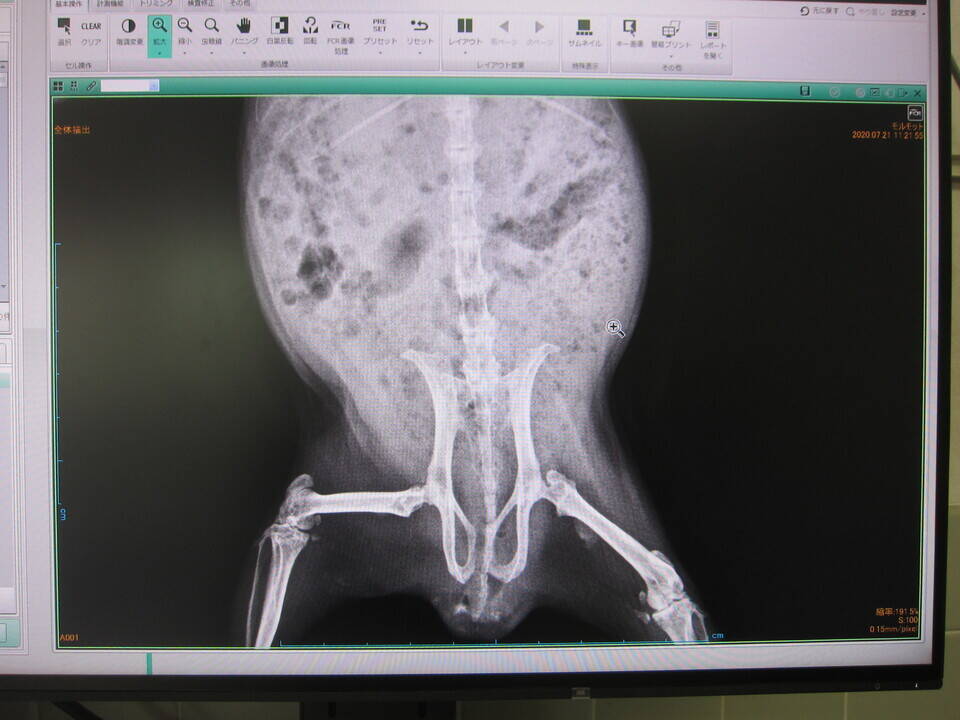

撮った画像がコチラ。

デジタルなので、パソコンのモニター上に映して診断します。

見たい部分を拡大したり、

陰影の濃淡を調整したり、

自由自在!なんて便利!